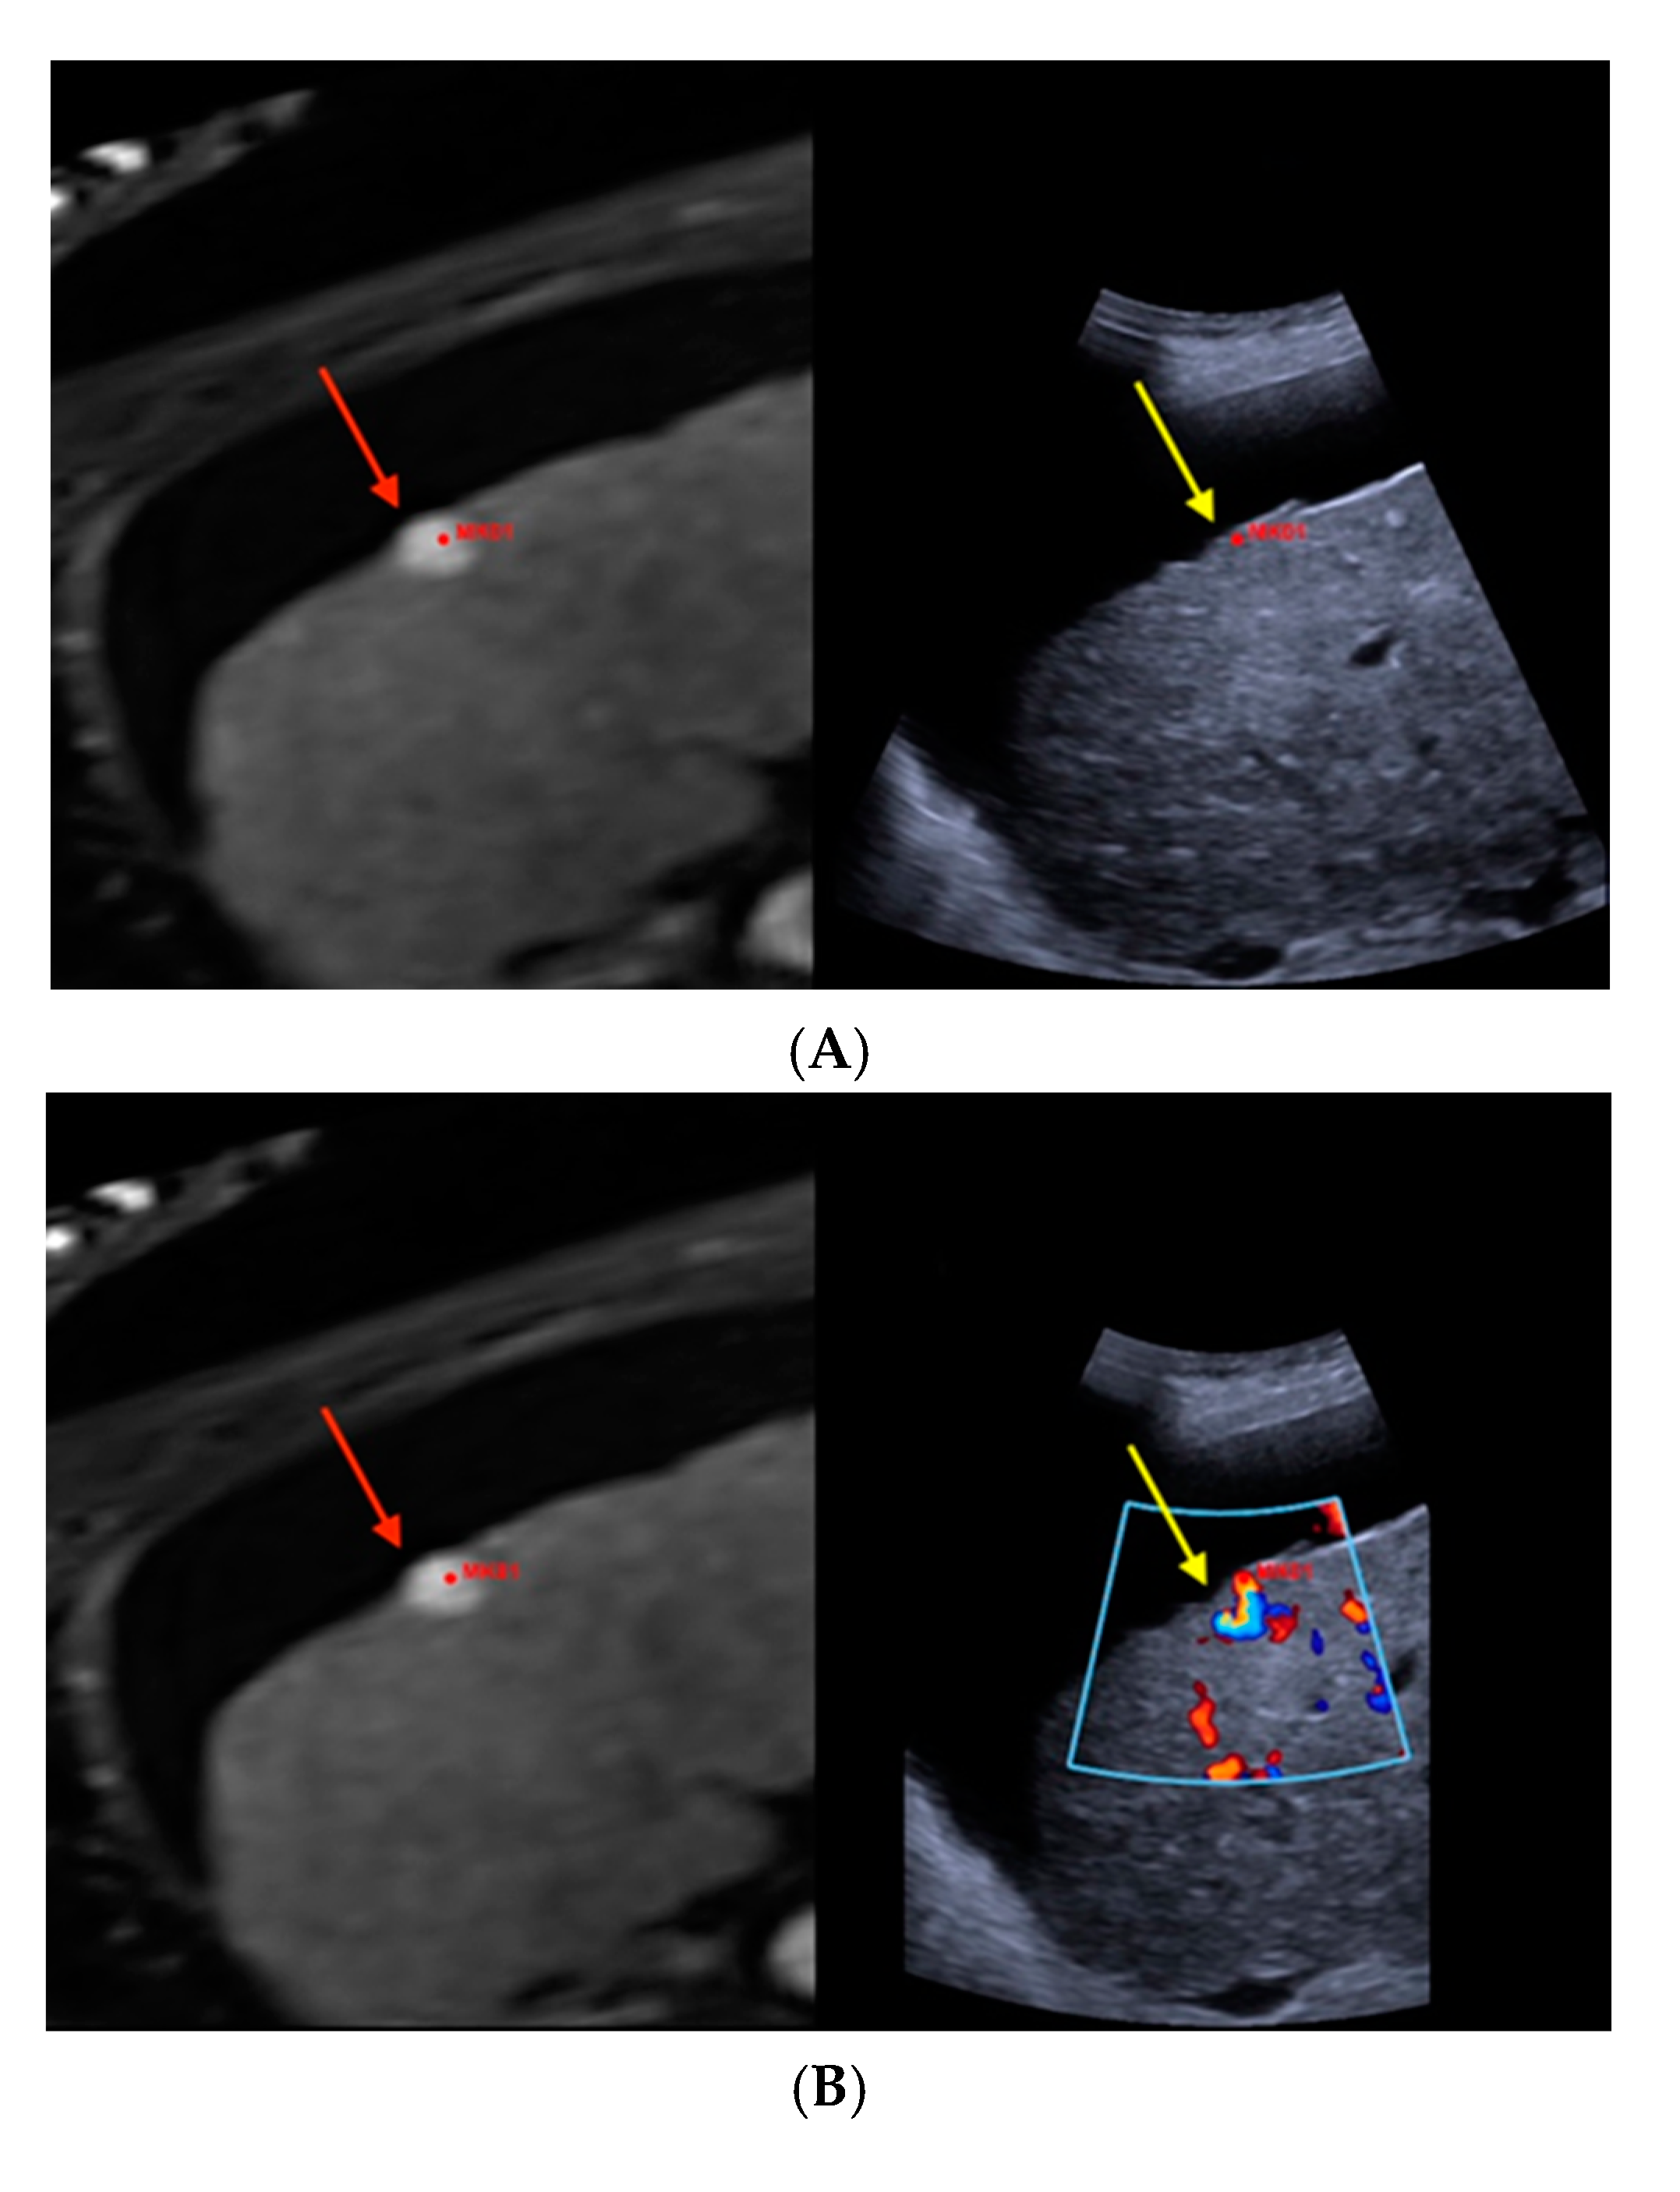

Figure 1 illustrates the MR-morphological correlate of a suspiciously hypervascularized focal liver lesion in a cirrhotic patient, which fusion imaging unraveled as underlying FNH.

Figure 1.

Real-time magnetic resonance imaging-/contrast-enhanced ultrasound (MRI-/CEUS)-fusion imaging of a hypervascularized focal liver lesion in a cirrhotic patient. (A) A hypervascularized subcapsular focal lesion in liver segment 7 was registered in MRI, arterial phase (left), a target lesion (MK01, red) was placed for precise correlation with native B-mode (right) in a side-by-side manner. The focal lesion otherwise was barely detectable by conventional ultrasound. (B) Additional Color Doppler showed livid hypervascularization of the lesion (right), a corresponding plane of MRI, arterial phase (left). (C) Peripheral-to-central contrast-enhancement and, finally, homogeneous contrast enhancement was registered in CEUS (left, maximized), implicating focal nodular hyperplasia. The software interface of the ultrasound device showed four different images: real-time CEUS images (left, maximized), MRI datasets in axial (upper right) and sagittal (middle right) reformation, and a real-time 3D navigation of the MRI-/CEUS-fusion imaging (lower right), (lesion marked by red arrows).